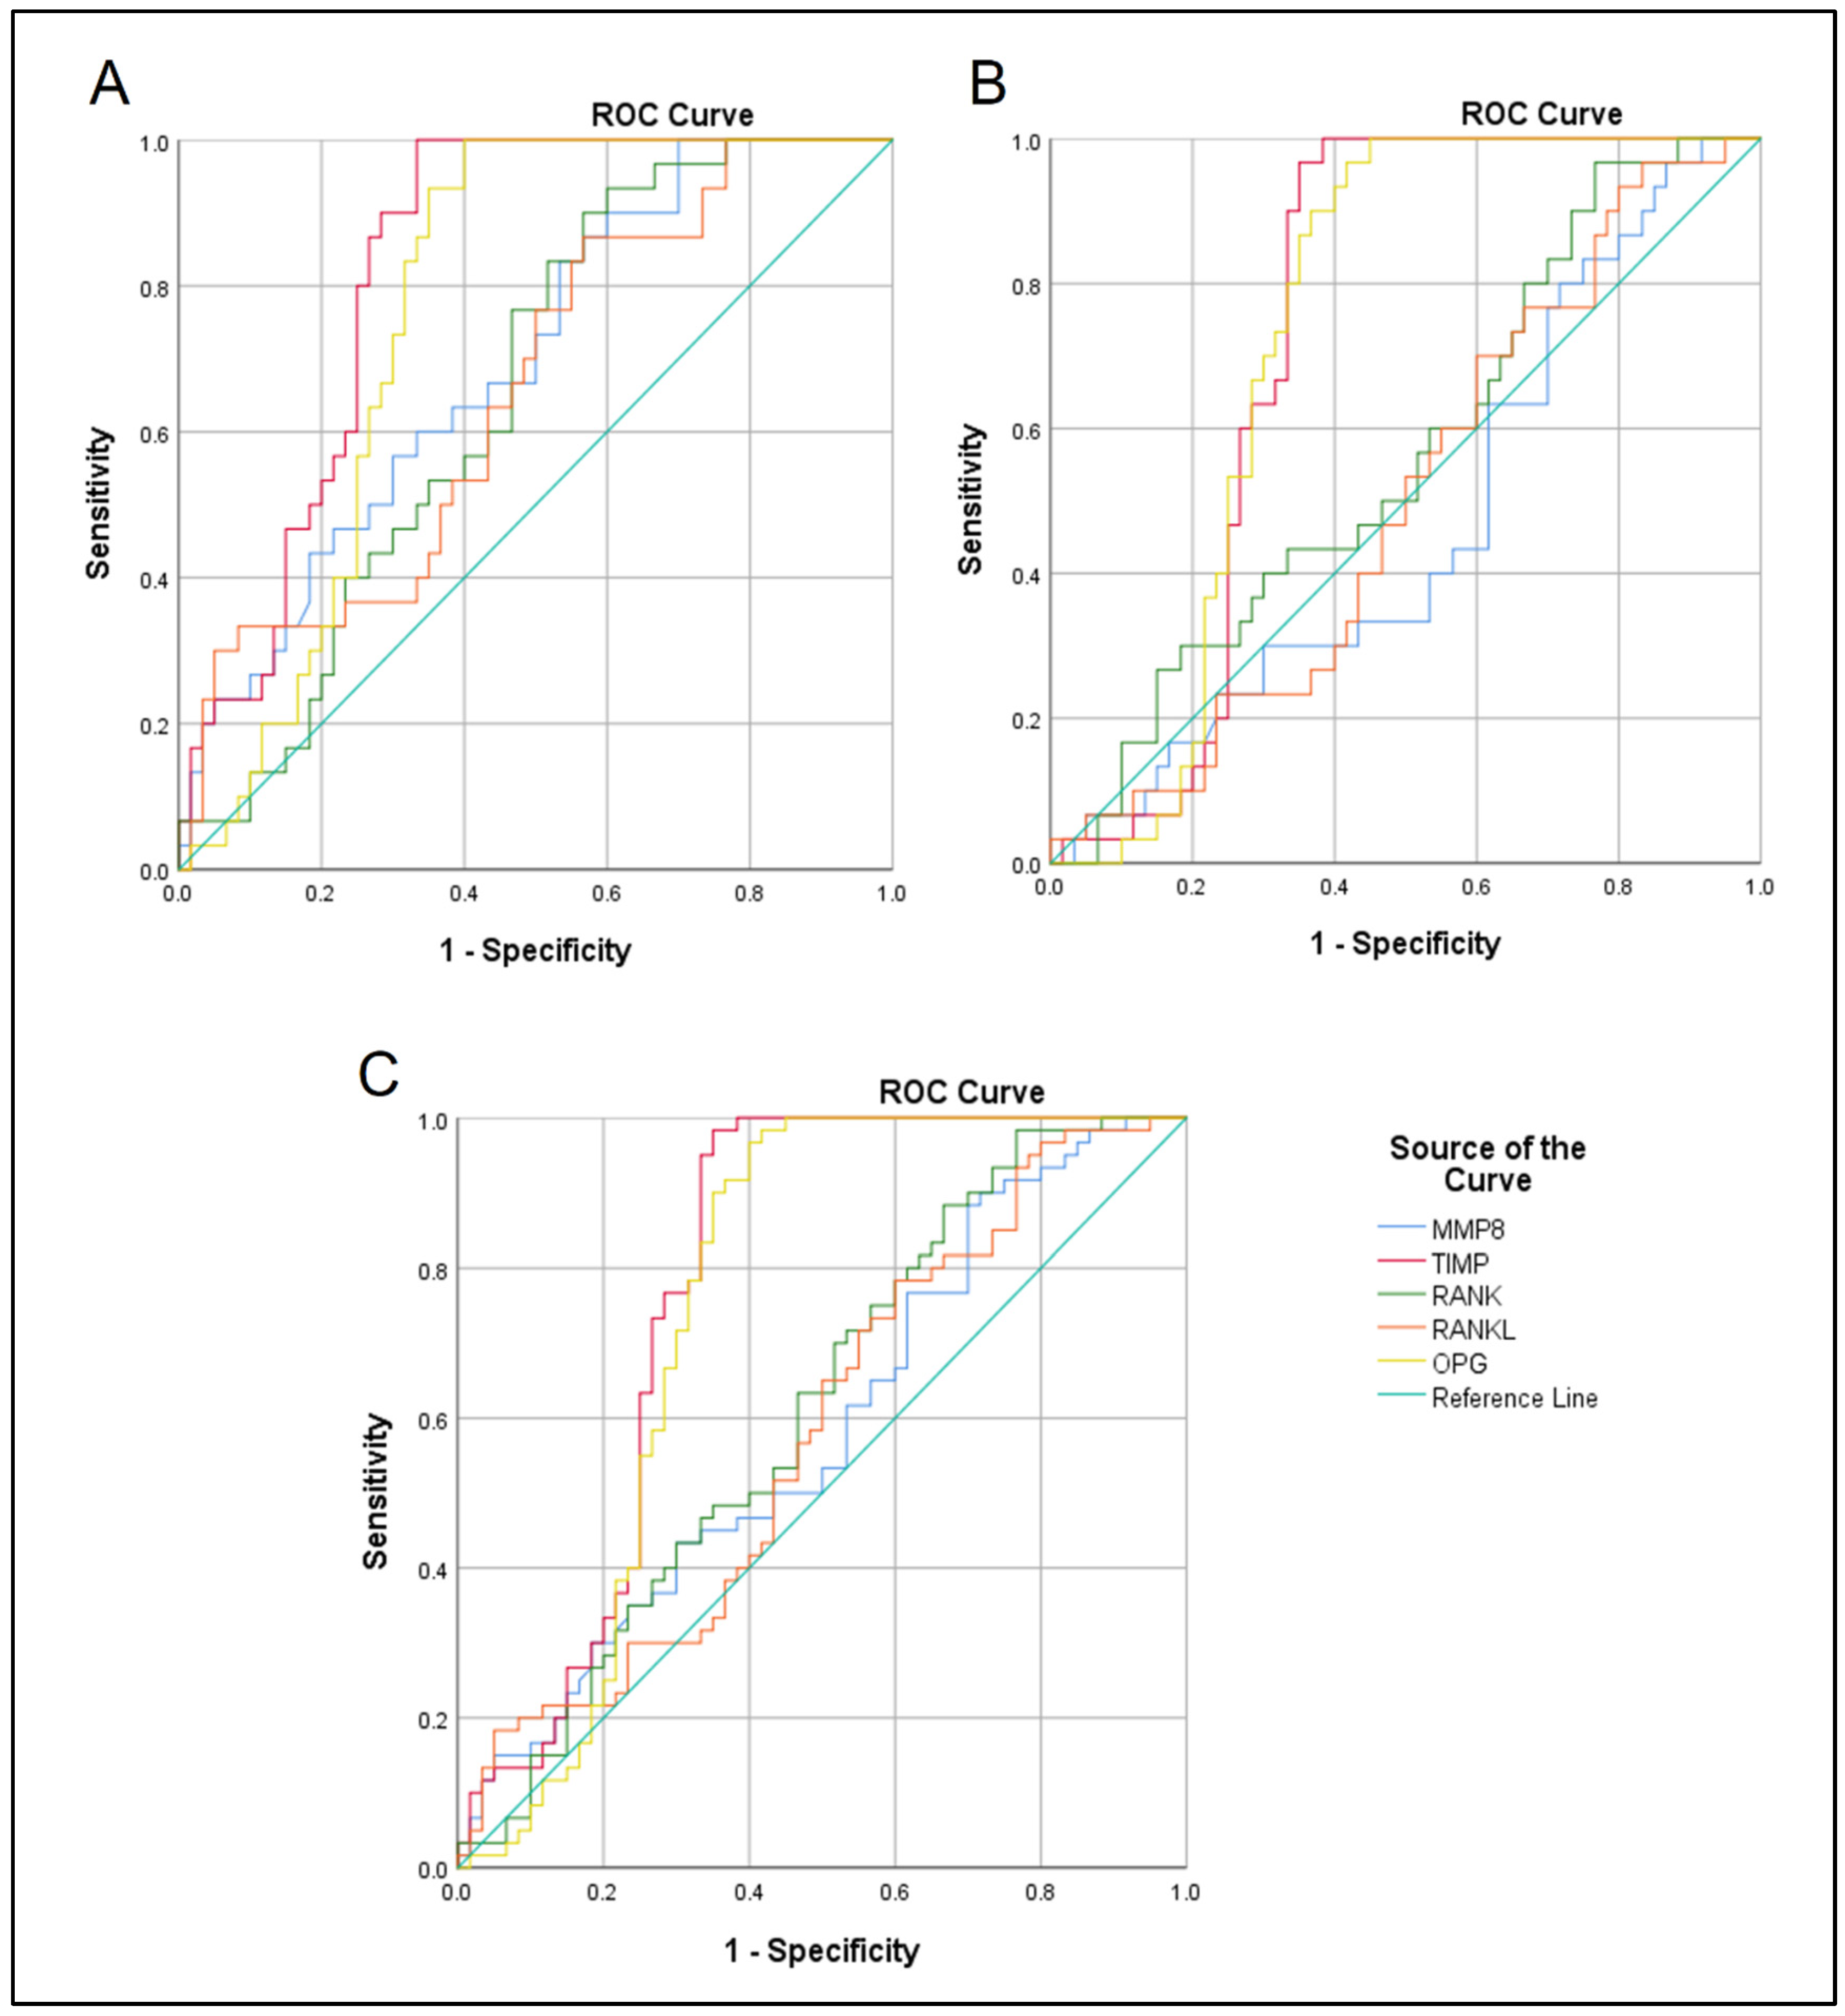

| Groups Comparison | Variables | Threshold µg/mL | Sensitivity%/Specificity% | AUC | 95% CI | p Value |

|---|---|---|---|---|---|---|

| SAP vs. control | MMP8 | 0.053 | 60/67 | 0.694 | 0.58–0.8 | 0.003 |

| TIMP1 | 8.64 | 80/75 | 0.824 | 0.74–0.9 | 0.0001 | |

| RANK | 0.31 | 60/57 | 0.652 | 0.54–0.76 | 0.019 | |

| RANKL | 1.27 | 57/57 | 0.656 | 0.53–0.77 | 0.017 | |

| OPG | 0.066 | 73/70 | 0.763 | 0.66–0.86 | 0.0001 | |

| AAP vs. control | MMP8 | 0.046 | 43/44 | 0.47 | 0.34–0.59 | 0.647 |

| TIMP1 | 7.46 | 66/67 | 0.732 | 0.62–0.83 | 0.0001 | |

| RANK | 0.26 | 56/50 | 0.562 | 0.44–0.68 | 0.338 | |

| RANKL | 1.16 | 53/49 | 0.502 | 0.38–0.62 | 0.973 | |

| OPG | 0.067 | 70/70 | 0.73 | 0.62–0.83 | 0.0001 | |

| SAP vs. AAP | MMP8 | 0.049 | 53/50 | 0.582 | 0.48–0.68 | 0.122 |

| TIMP1 | 7.78 | 75/72 | 0.778 | 0.68–0.86 | 0.0001 | |

| RANK | 0.29 | 53/54 | 0.607 | 0.51–0.71 | 0.043 | |

| RANKL | 1.21 | 56/54 | 0.579 | 0.47–0.68 | 0.136 | |

| OPG | 0.067 | 70/70 | 0.747 | 0.64–0.84 | 0.0001 |